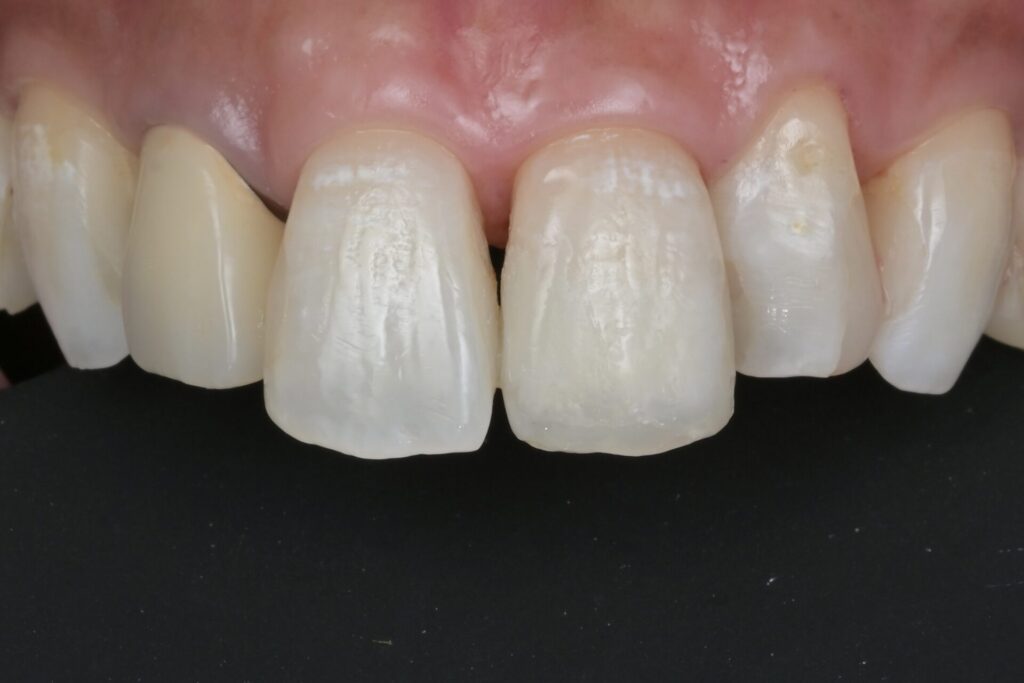

虫歯の治療・ダイレクトボンディング

40代 虫歯治療 ダイレクトボンディング #31

Before

After

| 年齢 | 40代 | 治療方法 | ダイレクトボンディング |

|---|---|---|---|

| 性別 | 女性 | 通院回数 | 2回 |

| 主訴 | できるだけ歯を削る量を少なくしてむし歯を治したい | 費用 | 231,000円(税込) |

| 治療のメリット | 歯を削る量を少なくできる・自然な見た目・境目がピッタリできる | ||

| 治療のデメリット | 大きい虫歯治療には適応できない場合がある | ||